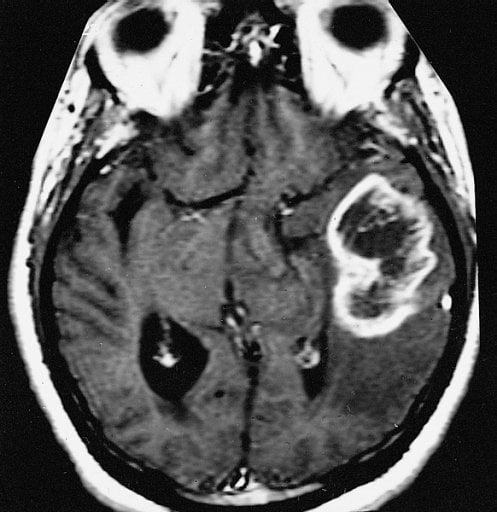

TCGA ganged up on glioblastoma multiforme (GBM), the most common and lethal of brain tumors, with more than 100 scientists from 14 institutions tracking down the genomic abnormalities that drive GBM.

About 23,000 new cases of GBM are predicted in the United States during 2013 and more than 14,000 people expected to die of the disease. Most patients die within 15 months of diagnosis.

Image Source: The MRI scan image is credited to The Armed Forces Institute of Pathology and is in the public domain.